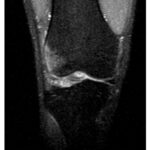

Hiperextensión

Imágenes sagitales y axial de secuencias potenciadas en T2 con saturación grasa de la rodilla derecha en paciente con lesión por hiperextensión. (a, b) Edema óseo en la vertiente anterior del tercio proximal de la tibia y del cóndilo femoral interno por impactación. (c) Rotura parcial del ligamento cruzado posterior (flecha).

Fuente: https://epos.myesr.org/posterimage/esr/seram2014/124014/mediagallery/576992

Patrones de lesión de rodilla | Caso de radiología | Radiopaedia.org. https://radiopaedia.org/cases/patterns-of-knee-injury

La hiperextensión forzada de la rodilla puede ser el resultado de una fuerza aplicada sobre la vertiente anterior de la tibia mientras el pie está plantado o “bloqueado”, o de una fuerza indirecta, por ejemplo, durante la acción de patear un balón. Las lesiones de mayor severidad en general son secundarias al trauma directo, originando un desplazamiento posterior de la tibia y cóndilos femorales, con distracciones severas en las estructuras posteriores de la articulación, así como la presencia de fracturas. Dependiendo del tipo y grado de fuerza aplicado sobre la articulación, podemos encontrar los siguientes hallazgos.[xxiii]

Hiperextensión pura

Patrones de edema óseo:

- Contusiones en la vertiente anterior de la tibia y/o vertiente anterior de los cóndilos femorales por impactación.

Lesiones de partes blandas:

- Rotura del ligamento cruzado posterior en los casos donde predomina el desplazamiento posterior de la tibia.

- Rotura del ligamento cruzado anterior en los casos donde predomina el desplazamiento posterior del fémur.

Hiperextensión con inclinación en valgo

- Contusiones en la vertiente anterolateral de la tibia, peroné y cóndilo femoral externo por impactación.

- Esquina posteromedial por avulsión/contragolpe.

- Desgarros del ligamento colateral medial, cápsula posterior, ligamento cruzado posterior.[xxiv]

Hiperextensión con inclinación en varo

- Contusiones en la vertiente anteromedial de la tibia y cóndilo femoral interno por impactación.

- Esquina posterolateral o peroné proximal por avulsión/contragolpe.

- Desgarros del ligamento colateral lateral, tendón poplíteo, cápsula posterior, ligamento cruzado anterior.